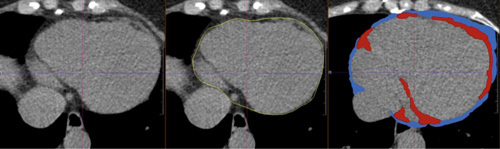

Materials and methods: All mechanically ventilated COVID-19 patients with an available chest computed tomography were prospectively included (March-June 2020). PF and EAT volumes were quantified using chest computed tomography scans. Patients were categorized into sex-specific PF and EAT tertiles. Variables to calculate Sequential Organ Failure Assessment (SOFA) scores were collected daily to indicate multiorgan failure. Linear mixed-effects regression was used to investigate the association between tertiles for PF and EAT volumes separately and serial SOFA scores over time. All models were adjusted.

Abstract Image